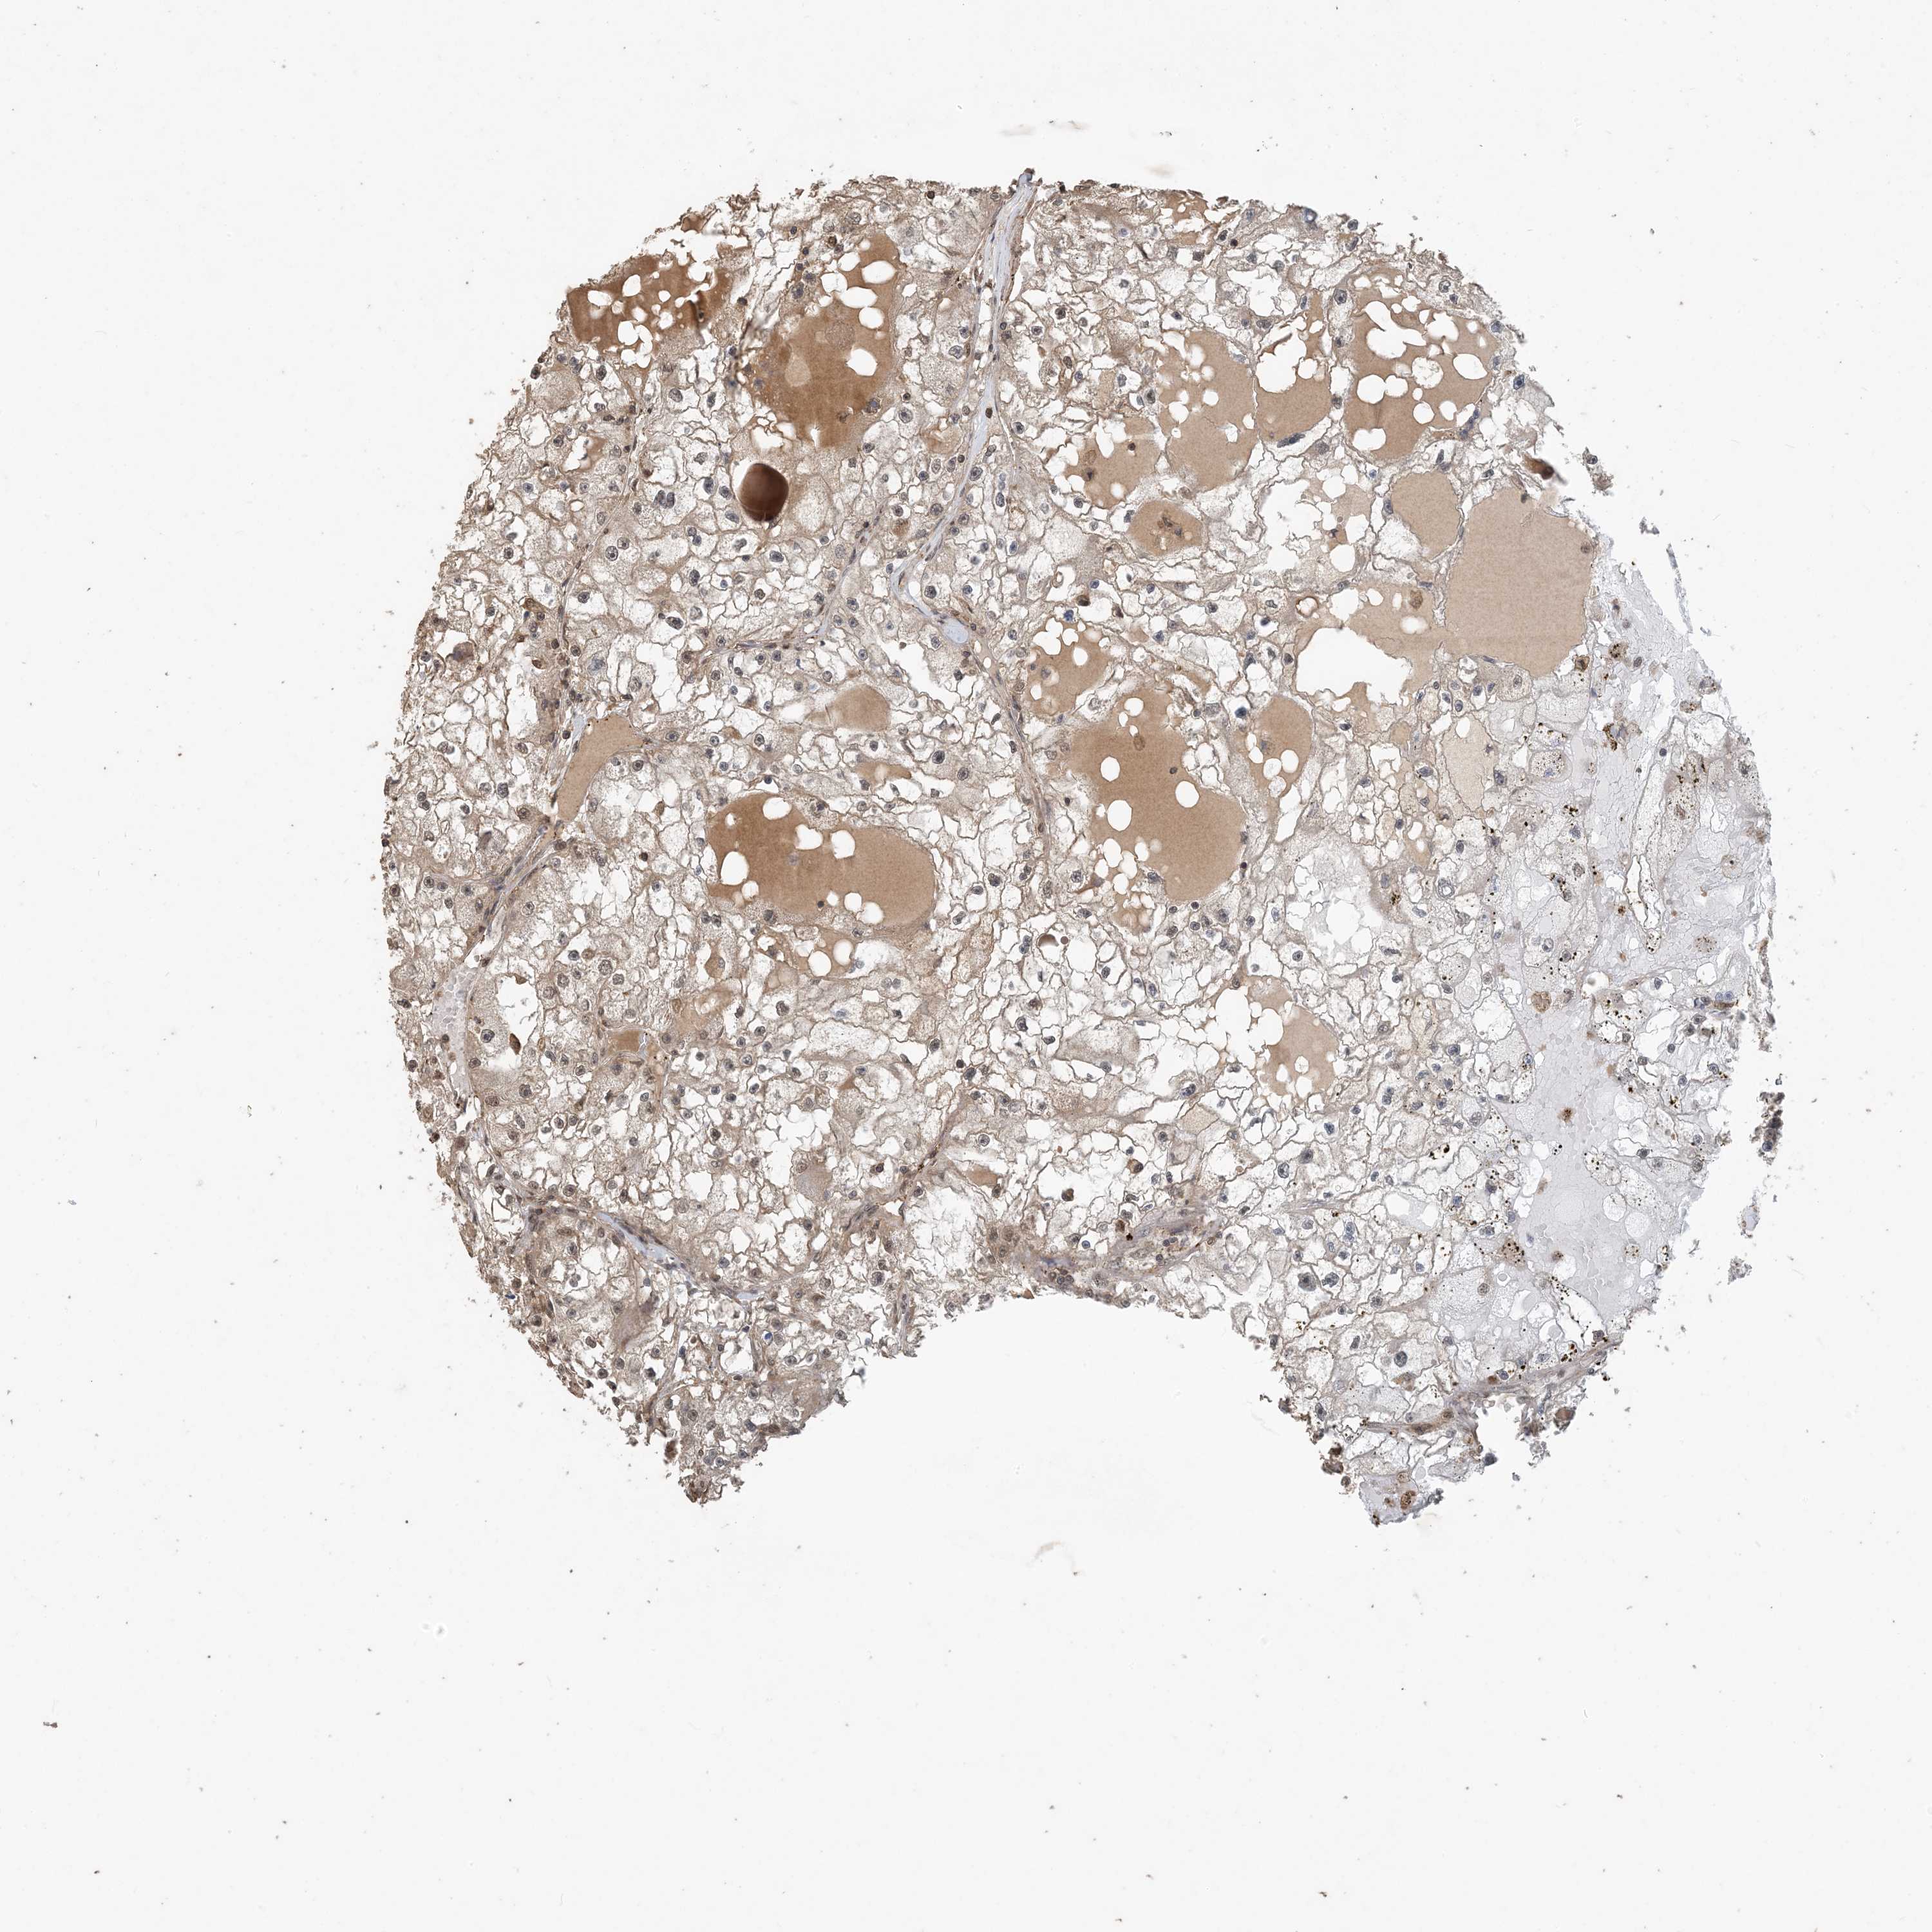

CANCER RENAL CANCER Show tissue menu

Kidney renal papillary cell carcinoma

KIDNEY RENAL CLEAR CELL CARCINOMA (VALIDATION) - Interactive survival scatter ploti

ZC3H12A is not prognostic in Kidney Renal Clear Cell Carcinoma (validation)

: 12.02

Average pTPM 8.4

Number of samples 100